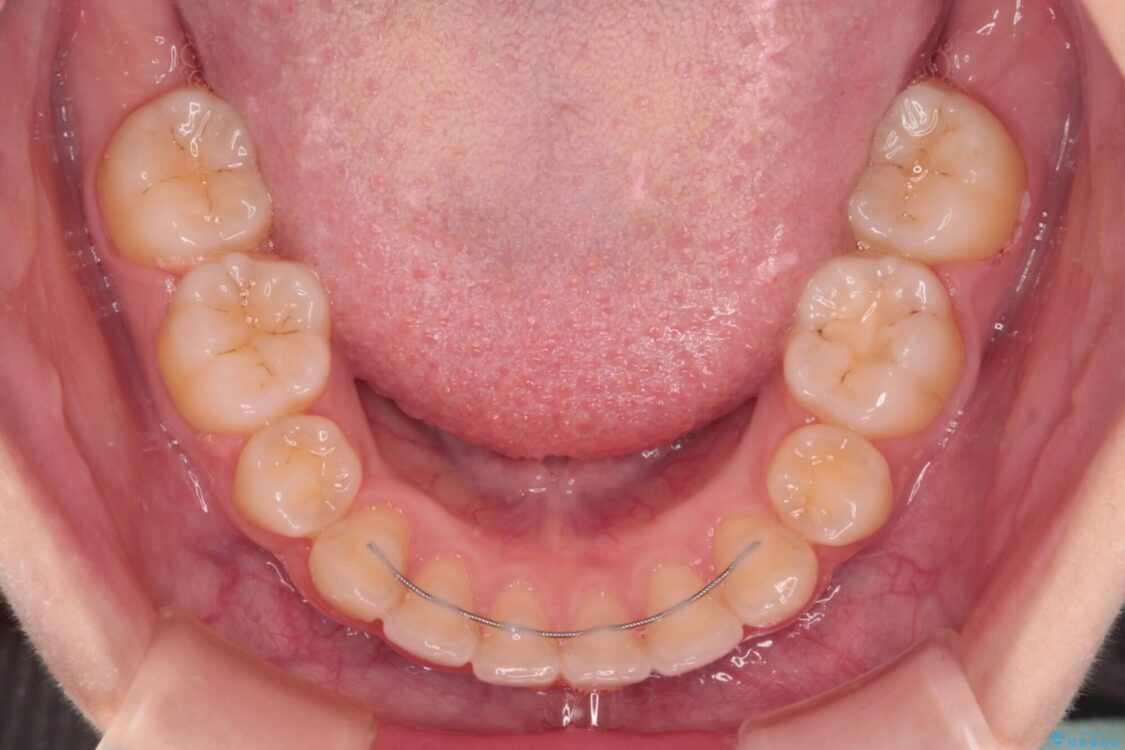

治療途中

• 【モニター】口が閉じられない ワイヤー装置での抜歯矯正 治療途中画像